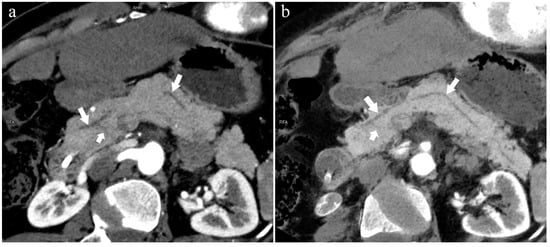

Figure 4.

Type 3b, 63-year-old male patient with AP. (a): MIP [45 keV MEI (+)] shows an S-shaped dilated MPD (long arrow) in the head of the pancreas. APD is not displayed. The fat space around the head of the pancreas is blurred (short arrow). (b): MinIP [45 keV MEI (+)] clearly shows the overall shape of “S”-shaped MPD.

Figure 5.

Type 1. A 68-year-old male patient with IPMN. (a): MIP [45 keV MEI (+)] shows a tumor (pentagram) and the dilated MPD (long arrow) in the head of the pancreas. APD (short arrow) drained from MiP and communicated with MPD. The common bile duct (arrow) is clearly visible. Postoperative pathology confirmed that the mass was IPMN. (b): MinIP [45 keV MEI (+)] clearly shows the overall direction of MPD.